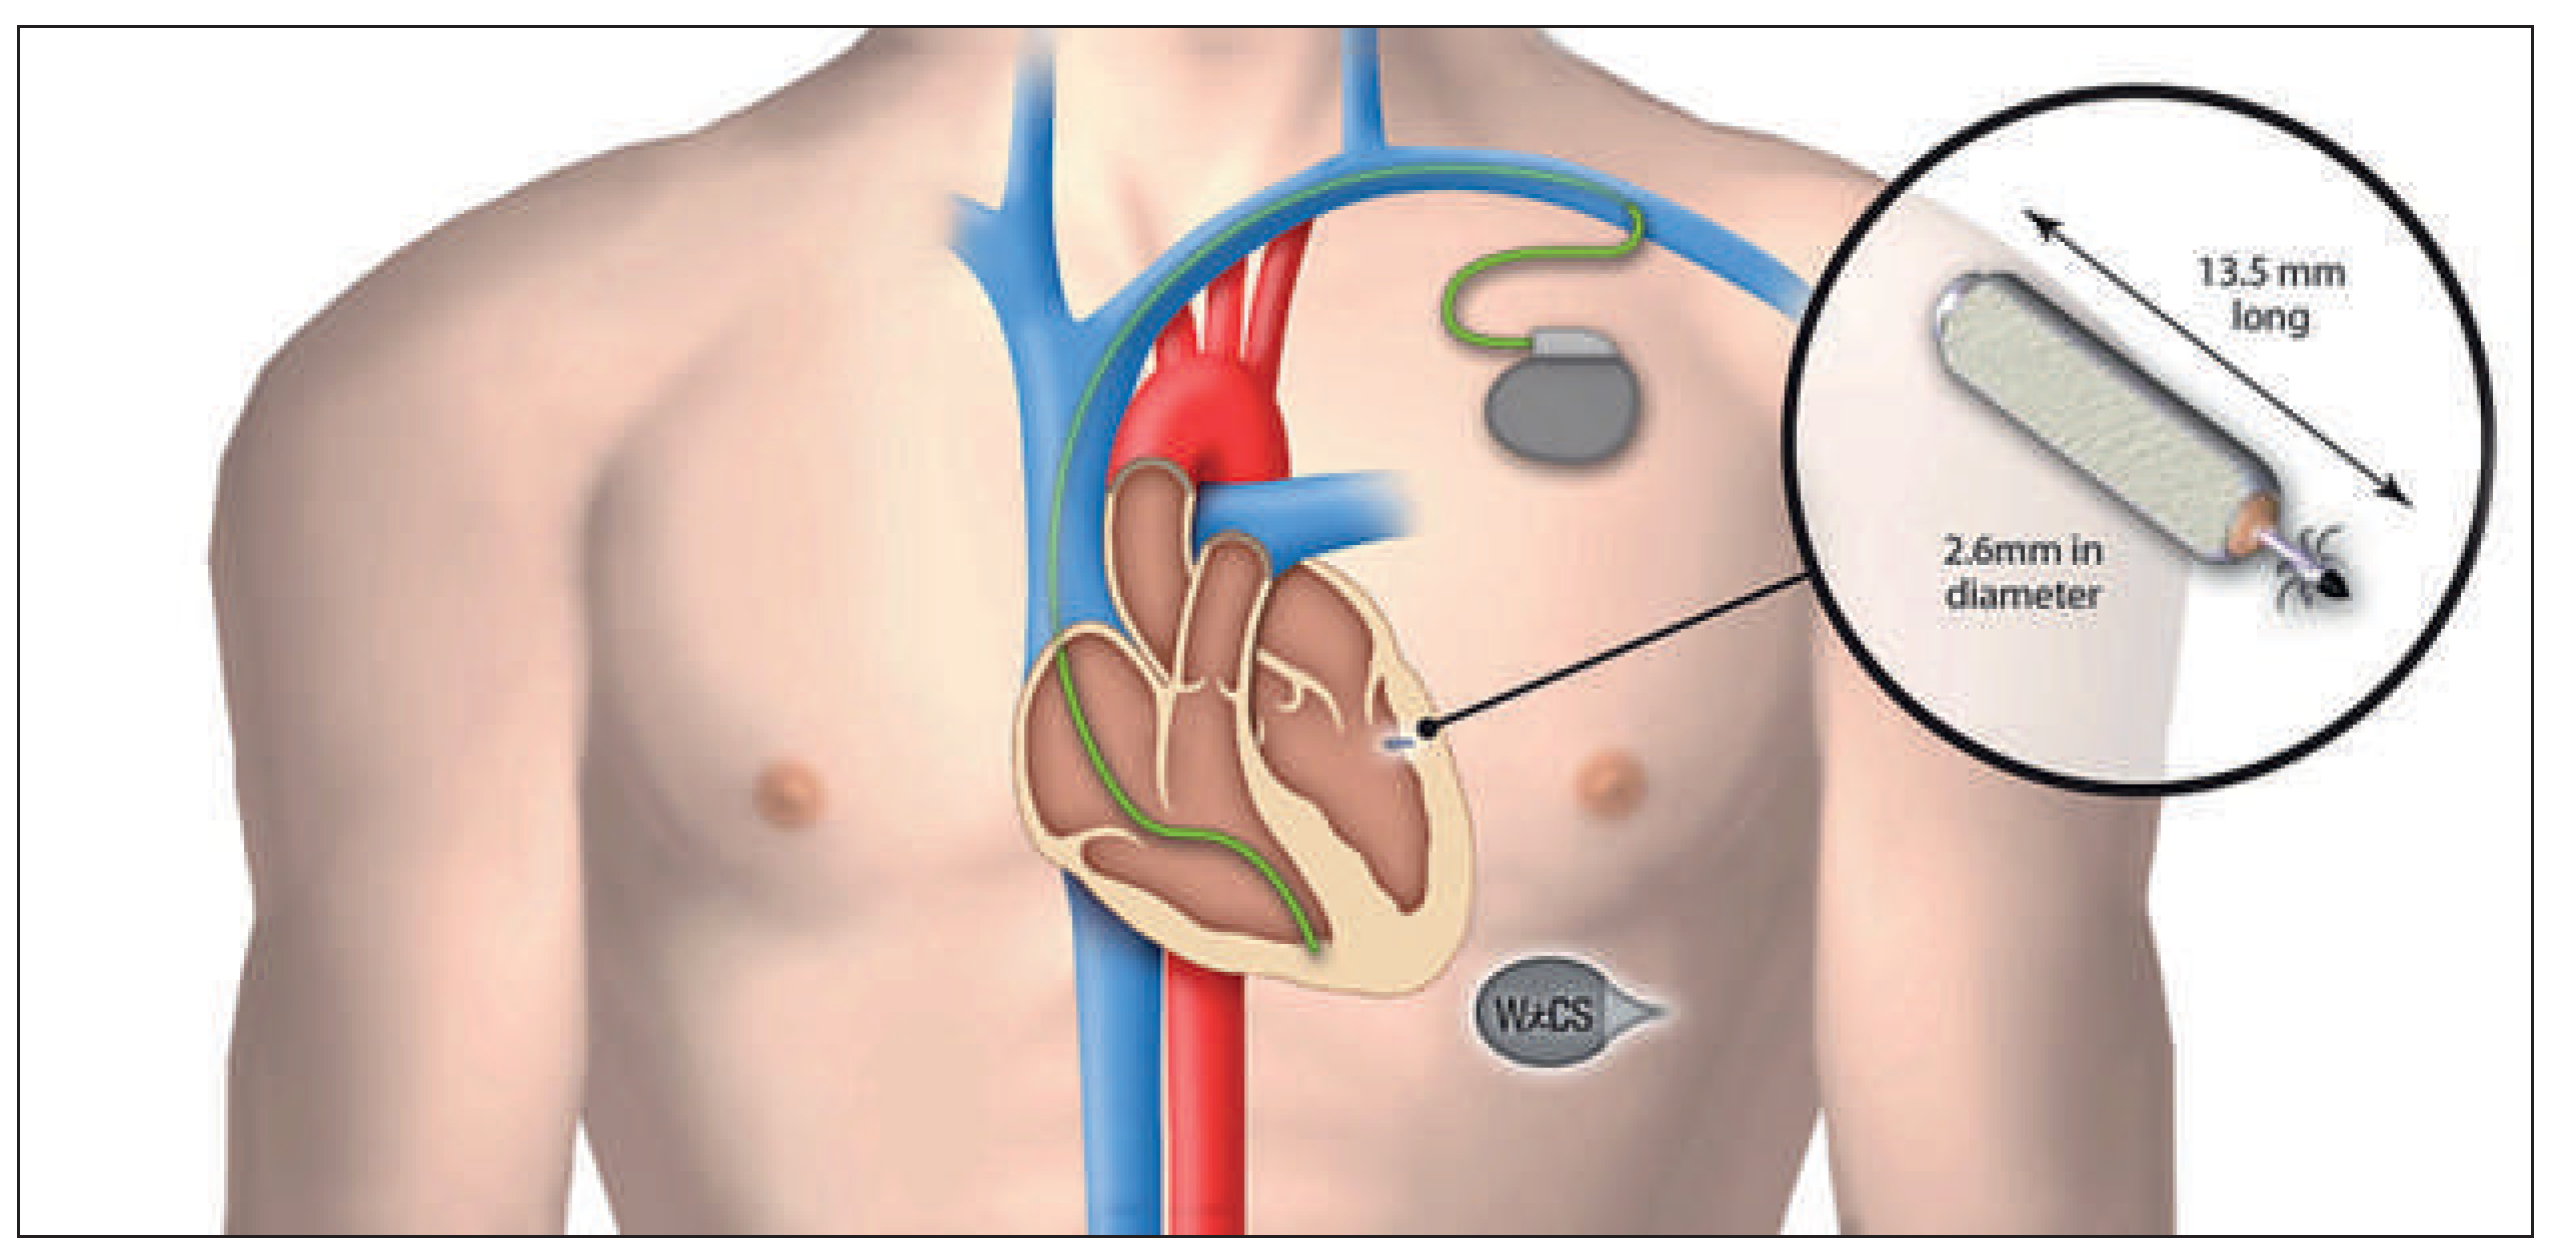

Right Ventricular Pacing Devices

Left Ventricular Pacing System

Implantation Procedures of Leadless Devices

Right Ventricular Pacing Systems

Wireless Cardiac Resynchronisation Therapy System